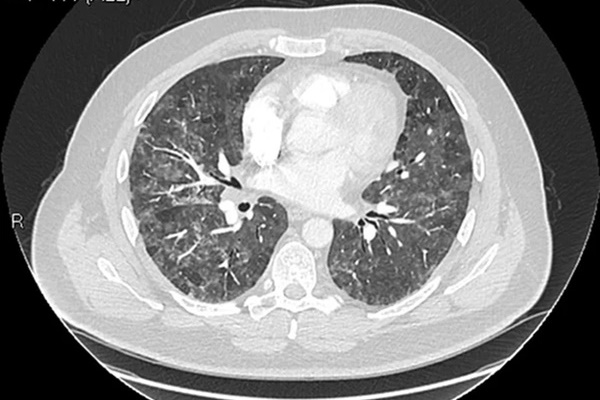

7. Phải kiểm tra sức khỏe định kỳ

Chú ý phát hiện các dấu hiệu của bệnh phổi từ rất sớm. Nếu phát hiện các bệnh lý về đường hô hấp cũng như các bệnh lý ở cơ quan khác thì phải đi thăm khám và tiến hành điều trị ngay.